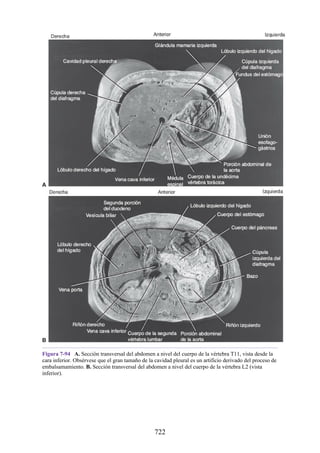

nervioso central por debajo de la cabeza.

Los nervios espinales (31 pares) se ramifican a los lados de la

médula espinal. Están formados por la fusión sucesiva de

raicillas y raíces anteriores y posteriores. Todos los nervios

espinales pasan a través de un foramen intervertebral y se

dividen en los ramos anterior y posterior.